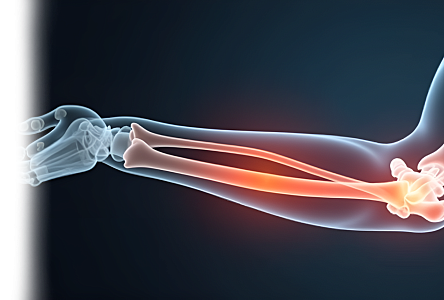

УЗИ локтевого сустава

УЗИ локтевого сустава – безопасный и неинвазивный метод исследования, который позволяет оценить состояние мягких тканей и структур локтевого сустава.